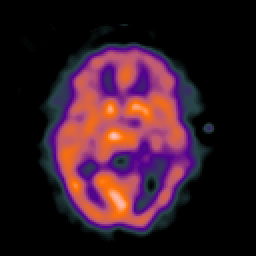

SPECT TC Study #5 -- Slice #27

[Home][Help][Clinical][Tour 1][Tour 2][Tour 3] Slice 27